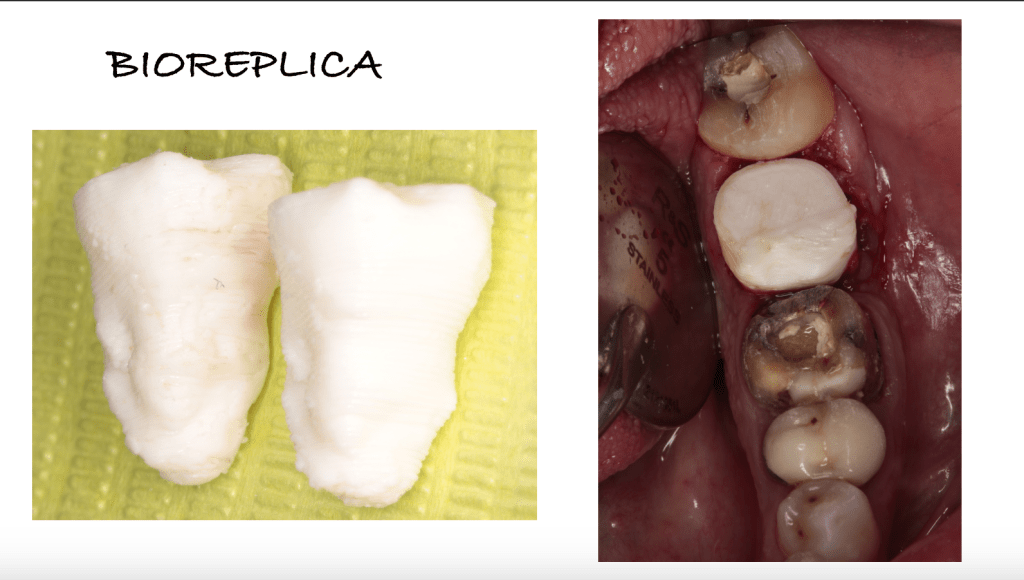

REIMPLANTES

Intencional por dificil acceso coronal y quirúrgico

Reinplante por fracaso de tratamiento

Reimplante, istmo apical, curación cortical palatina 1 año